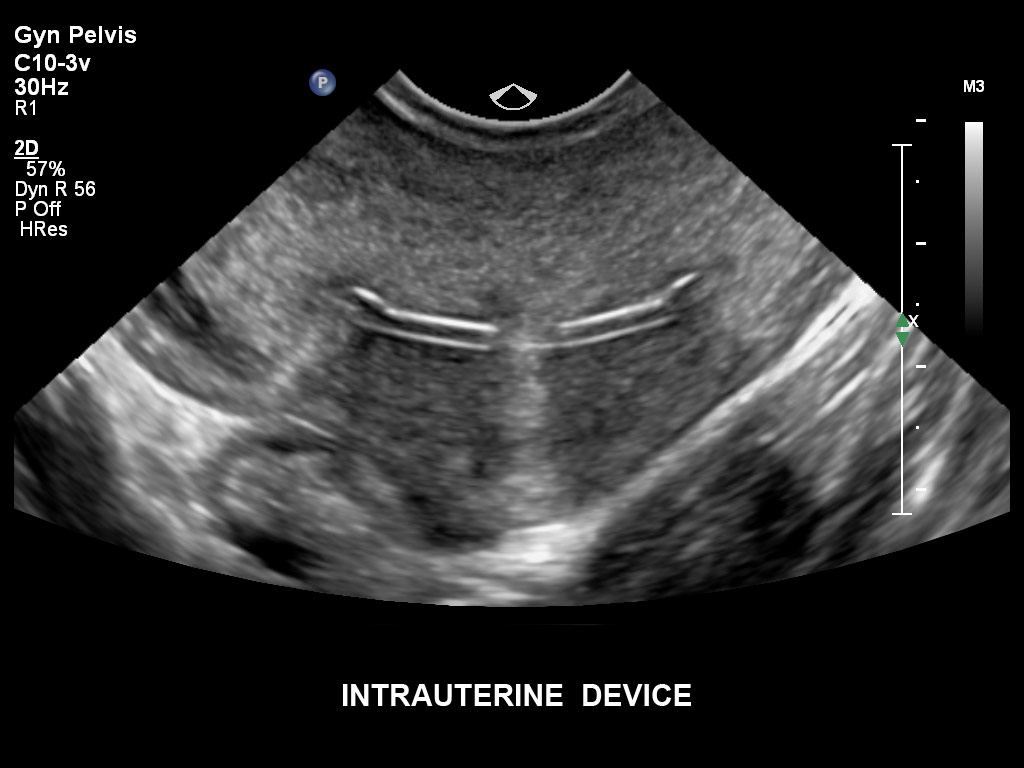

• C10-3v PureWave-Breitband-Endo-Convex-Schallkopf, ideal für anspruchsvolle Myom- und komplexe Ovar-Untersuchungen sowie Bildgebung im ersten Schwangerschaftstrimester